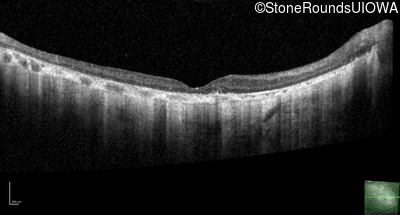

Optical Coherence Tomography - Left - 20/250 sc

Exemplar / OCT Stack